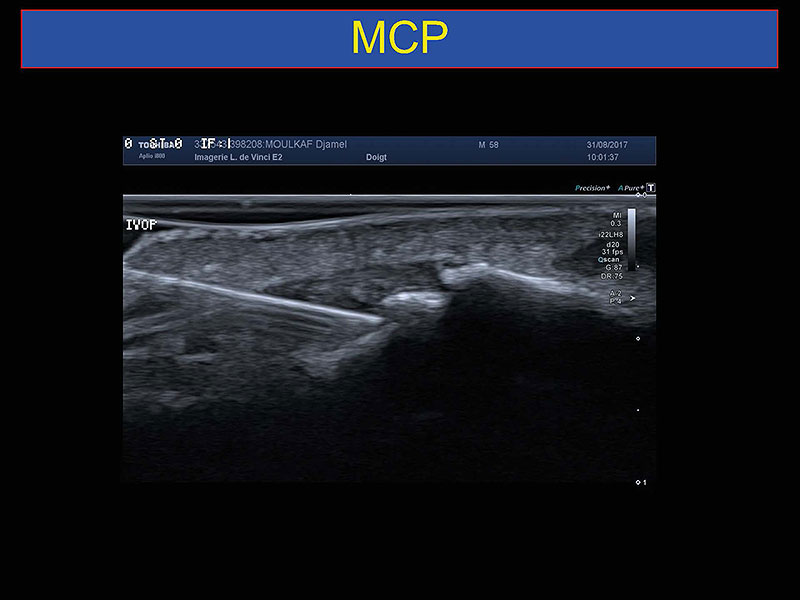

Traitements échoguidés des pathologies du poignet et de la main

Dr H.Guerini (Paris)